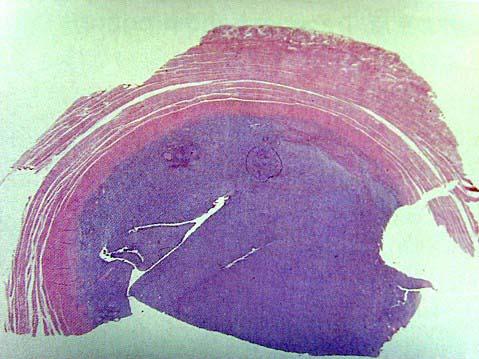

问题 女性,28岁,因下腹不适检查,扪及下腹部包块,行子宫切除术。大体见子宫肌壁间灰白、灰黄结节,直径2cm,边缘清楚。显微镜下见肿瘤细胞大小较一致,染色均匀,核分裂像少见,3个/10HP,肿瘤富于血管,无血管浸润。免疫组化DES(-)、CD10(+)。应诊断为 ( )

选项 A.子宫平滑肌瘤 B.子宫平滑肌肉瘤 C.子宫未分化肉瘤 D.子宫内膜间质结节 E.子宫内膜间质肉瘤

答案 D